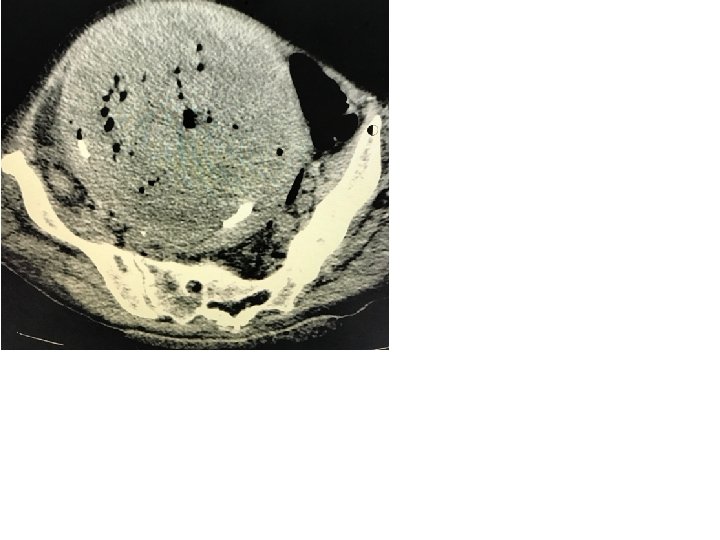

Paciente de 68 anos, com história de tratamento recente de infecção urinária, febre há 7 dias e dor forte no baixo ventre. Ao exame físico: paciente febril ao toque, com muita dor abdominal e tomuração pélvica palpável. Conduta: USG → TC de abdome Scalt da TC= RX que a TC faz Lesão radiopaca com calcificação